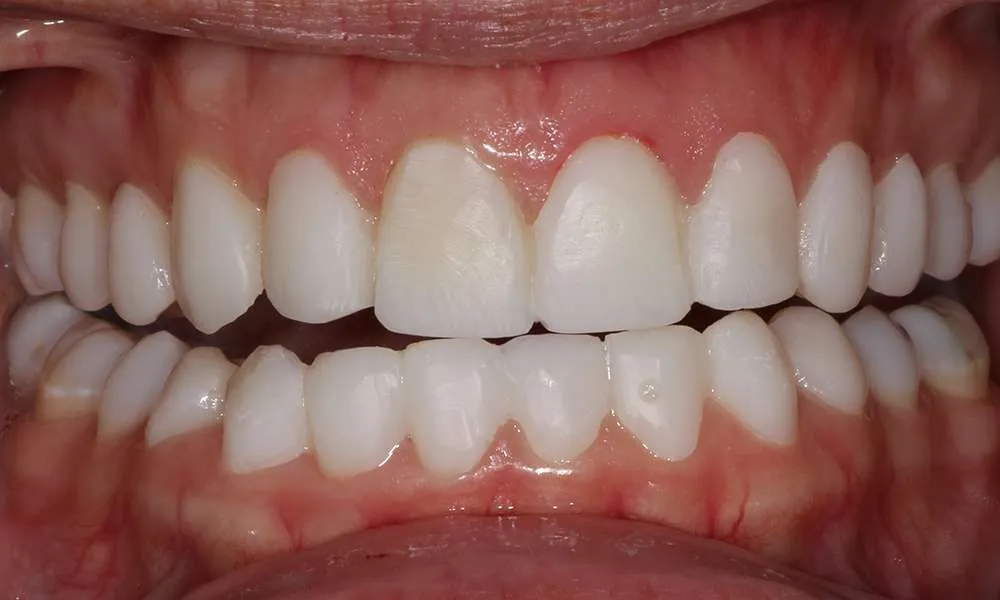

Ultra-thin veneers are crafted from high-quality materials that closely resemble the look and feel of natural teeth. The translucency and texture of these veneers mimic the appearance of real enamel, ensuring that your smile looks natural and aesthetically pleasing. Each veneer is custom-made to match the color, shape, and size of your existing teeth, blending seamlessly with your natural smile. This attention to detail ensures that your veneers are virtually indistinguishable from your natural teeth, providing you with a flawless, beautiful smile.

Complex Cases

Witness the Remarkable Changes We Can Achieve